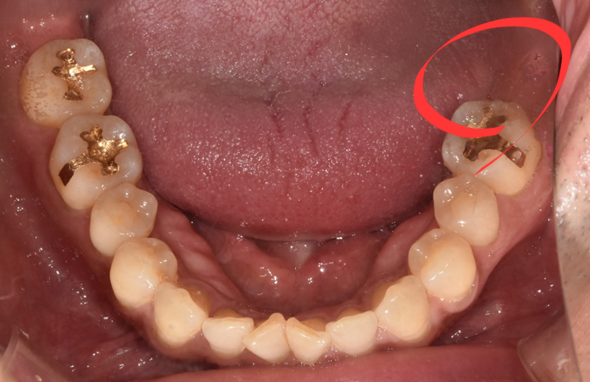

(후) 2022-01-11

이분은 SCRP 방식이라고 해서 보철물 분리가 가능한 타입으로 진행해 드렸는데요.

자세히 보시면 크라운 중앙에 구멍이 뚫려있는 것이 보이실 것입니다.

나중에 보수가 필요할 때 레진만 제거한 후 헐거워진 나사를 조이거나 풀 수 있고, 청소한 후 다시 씌우 수 있다는 장점이 있습니다.

한번 붙인 보철물도 언제든지 수정이 가능하다는 점 때문에 장기적으로 유지관리 측면에서 장점이 많은 방식입니다.